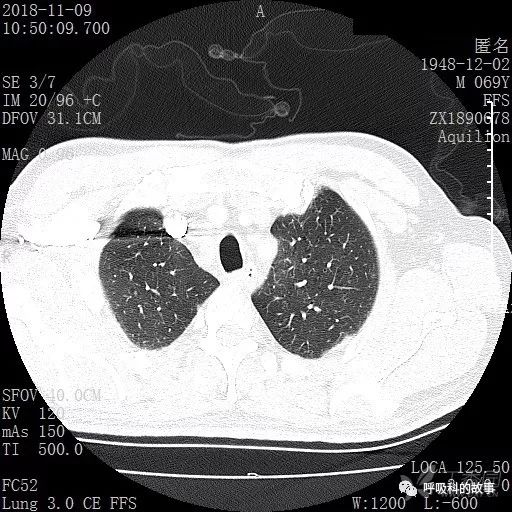

胸部增强CT示右肺门占位伴远端阻塞性肺炎,纵膈、右肺门、右侧颈根部、右侧腋下及肝门部肿大淋巴结。两侧胸腔少量积液。

肺窗CT